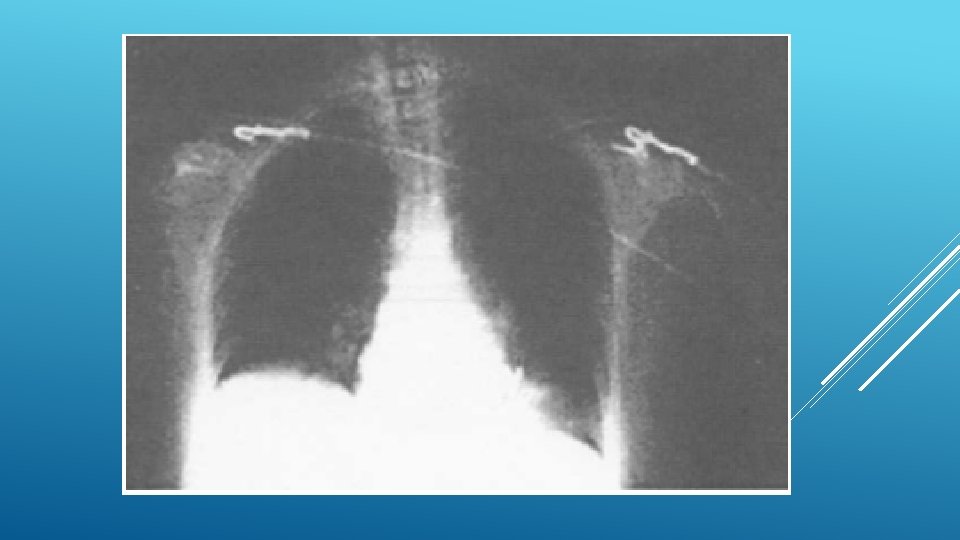

8. La radiographie thoracique vous est fournie. Quelle est votre interprétation ? • Cardiomégalie développée aux dépens du VG (aspect globuleux) • Ectasie pariétale VG (anévrisme du VG) • Épanchement pleural droit